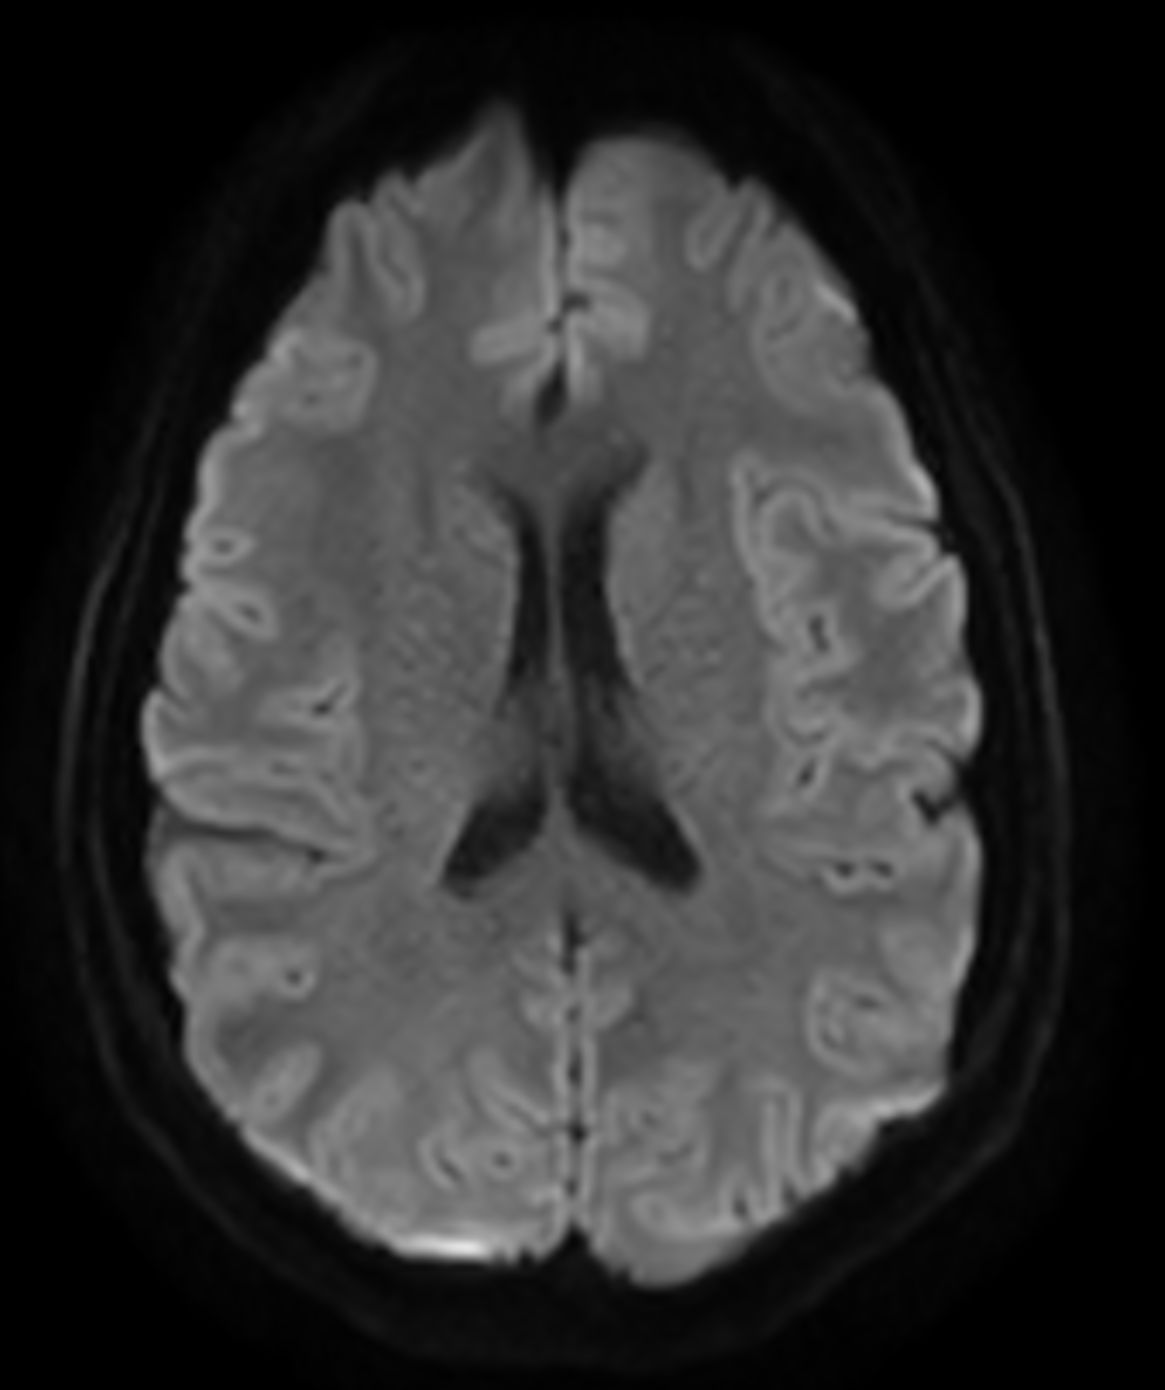

Alzheimer’s Disease Anti-Amyloid Immunotherapies (ARIA) 3.0T

Amyloid clearing medication, such as Aduhelm (Aducanumab) and Leqembi (Lecanemab) have been cleared by the FDA in 2022/2023, to slow down cognitive decline in early-stage Alzheimer’s disease. ASNR-recommendations for AD therapeutic imaging were published in 2022 for eligibility assessment as well as for monitoring for amyloid-related imaging abnormalities. This ExamCard includes ASNR-recommended consensus protocols for imaging of Alzheimer’s Disease Anti-Amyloid Immunotherapies (ARIA). (Cogswell et al., AJNR 2022,43(9)E19-E35;DOI: https://doi.org/10.3174/ajnr.A7586))